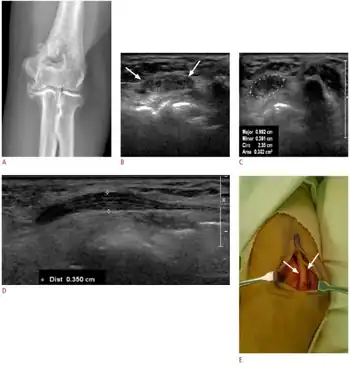

| Radial nerve compression is an example of nerve compression syndrome | |